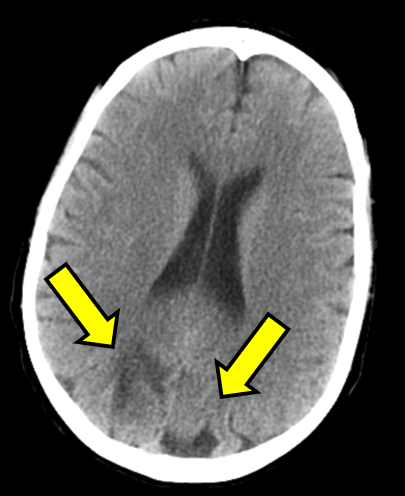

A few hours after admission she ultimately eloped during shift change. She returned to the same ED the next day after being found unresponsive outside again, was given Narcan en route as well as in the ED for bradypnea, and ultimately started on a naloxone drip, though she remained saturating well on room air. The initial temperature was 97.8°F and the initial BP was 121/83. Repeat head CT demonstrated the same vasogenic edema as seen previously (see Figure 1B). The patient was admitted again and remained normotensive. MRI with and without contrast demonstrated expansile T2/FLAIR hyperintense signal in the posterior frontal and parietal lobes, favored to be PRES (see Figure 1C and D).

Figure 1: Computed Tomography and Magnetic Resonance Imaging Demonstrating Posterior Reversible Encephalopathy Syndrome (PRES) Figure Caption: Initial (A) and next-day (B) CT imaging of concerning for PRES, with bilateral parietal vasogenic edema noted. MRI demonstrated expansile T2/FLAIR hyperintense signal in the posterior frontal and parietal lobes, favored to be PRES (C and D). Arrows correspond to areas of interest.

Initial (A) and next-day (B) CT imaging of concerning for PRES, with bilateral parietal vasogenic edema noted. MRI demonstrated expansile T2/FLAIR hyperintense signal in the posterior frontal and parietal lobes, favored to be PRES (C and D). Arrows correspond to areas of interest.